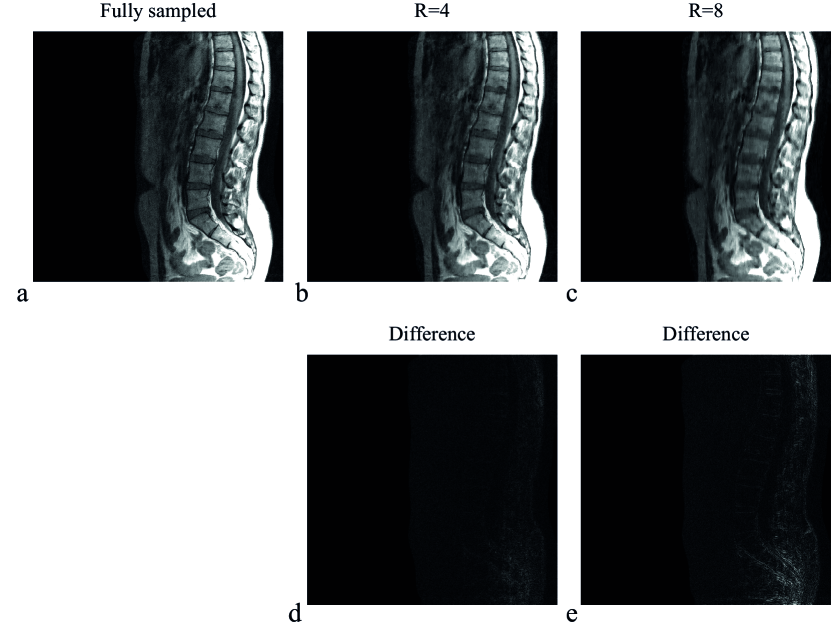

Figure 3 shows the T1-weighted TSE spine images for a reconstruction matrix size of 512×512512512512\times 512, reconstructed with the SB implementation for a fully sampled data set and for undersampling factors of four (R=4) and eight (R=8), where Cartesian sampling masks were used. The quality of the reconstructed images for R=4 and R=8 demonstrate the performance of the compressed sensing algorithm. The difference between the fully sampled and undersampled reconstructed images are shown in Fig. 3d and Fig. 3e for R=4 and R=8, respectively.

Figure 3: Reconstruction results for different Cartesian undersampling factors. (a) shows the fully sampled scan as a reference, whereas (b) and (c) depict the reconstruction results for undersampling factors four (R=4) and eight (R=8), respectively. The absolute difference is shown in (d) and (e) for R=4 and R=8, respectively. The reconstruction matrix has dimensions 512×512512512512\times 512. Regularization parameters where set to μ=1103,λ=4103formulae-sequence𝜇1superscript103𝜆4superscript103\mu=1\cdot 10^{-3},\lambda=4\cdot 10^{-3}, and γ=1103𝛾1superscript103\gamma=1\cdot 10^{-3}.